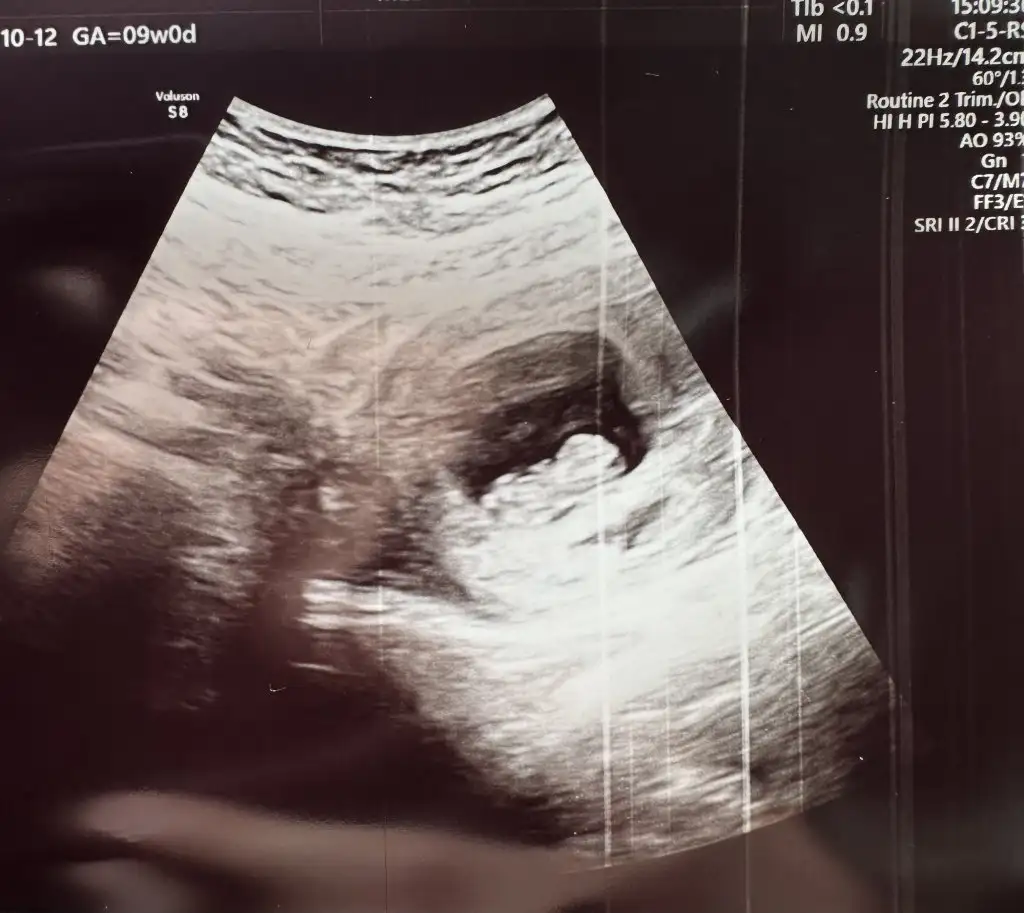

Tahmin bilmem de ben bu miniği yerim kasası eli belli bunun yaaaKızlar selam bugün doktora gittim 9+3 olduk, rica etsem cinsiyet tahmini yaparmısınızkarından bakıldıEki Görüntüle 3245733 Eki Görüntüle 3245733

Ramzi teorisine göre kiz canım Allah sağ salim kucagina almayı nasip etsinKızlar selam bugün doktora gittim 9+3 olduk, rica etsem cinsiyet tahmini yaparmısınızkarından bakıldıEki Görüntüle 3245733 Eki Görüntüle 3245733